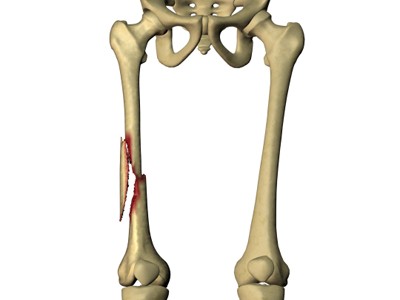

شکستگی استخوان فمور انواع مختلفی دارد که برحسب نیروی عامل شکستگی ایجاد میشود. ممکن است قطعات استخوان شکسته جابجا نشود یا این که قطعات شکسته جابجا شود؛ همچنین شکستگی گاهی بسته است و پوست آسیبی نمیبیند، اما گاهی باز است و استخوان از پوست بیرون میزند.

- محل شکستگی: بدنه استخوان ران به سه منطقه دیستال، میانی، پروکسیمال تقسیمبندی میشود.

شایعترین نوع شکستگیهای بدنه استخوان ران عبارت است از:

شکستگی عرضی

شکستگی عرضی نوعی شکستگی به صورت خط افقی صاف است که از بدنه استخوان ران رد میشود.

شکستگی مایل

شکستگی مایل به صورت خطی مورب در عرض بدنه استخوان ایجاد میشود.

شکستگی مارپیچ

خط شکستگی، مانند خط رنگی روی آب نبات چوبی، دور بدنه استخوان میپیچد. وارد شدن نیروی چرخشی به ران باعث این نوع شکستگی میشود.

شکستگی چندتکهای

استخوان در شکستگی چند تکهای به سه یا چند قطعه میشکند. تعداد قطعات استخوان در اکثر موارد تابعی از شدت نیرویی است که باعث شکستگی شده است.

شکستگی باز

اگر استخوان به شکلی بشکند که قطعات استخوان از پوست بیرون بزند یا زخم تا استخوان شکسته پیش برود، شکستگی از نوع باز یا ترکیبی خواهد بود. شکستگیهای باز غالباً آسیب بسیار بیشتری به رباطها، تاندونها و عضلات اطراف میزند. در شکستگی باز احتمال بروز عوارض، به ویژه عفونت، بیشتر است و زمان التیام نیز طولانیتر است.